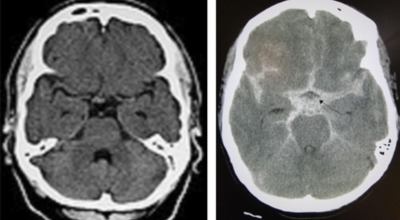

뇌출혈이란 뇌혈관의 출혈이 원인이 되어 일어나는 뇌혈관장애, 뇌일혈이라고도 그러나, 이는 갑작스러운 의식 장애, 이완성 반신불수 등을 유발하는 뇌졸중을 유발하는 대표적인 질환이예요. 뇌출혈의 대부분의 원인은 고혈압증이 원인이지만 드물게 백혈병이나 재생불량성 빈혈 과 같은 혈액질환과 함께 종양, 외상, 매독 등이 원인이 됩니다.

고혈압성 뇌출혈의 원인은 고혈압만이 아니라 터지기 쉬운 상태의 혈관에도 있다고 생각이 가능하지만, 아직까지 발생병리는 완전히 해명이 되지 않은 상태예요. 현재 생각 되는 것은 뇌내세 소동맥, 보통과 다르게 분기부의 혈관벽에 변화가 일어나서 연약해진 곳이 내압을 이겨내지 못하고 팽배해서 터져서 출혈을 한다는 것이죠. 뇌출혈이 일어나는 장소는 내포 부근이 가장 많다고 하며 이 부분의 중대뇌동맥의 가지가 터져서 출혈해요.

뇌출혈의 원인은 아주 다양한것으로 알려져 있답니다. 그중에서 가장 가장 저명한 뇌출혈 까닭으로는 고혈압을 꼽을 수 있습니다. 뇌출혈 발생원인이 되는 약 70%를 차지하는 고혈압은 혈관내 압력이 높은채로 쭉되게되면 세동맥혈관이 괴사되어 미세동맥류가 되는데 이는 파열되어 뇌출혈을 발생시킬 수 있죠. 그리고 외부의 쇼크으로 인한 뇌출혈도 생기게 될 수 있다고 하며, 당뇨, 뇌동맥류, 뇌종용과 같은 다양한 원인이 있답니다.